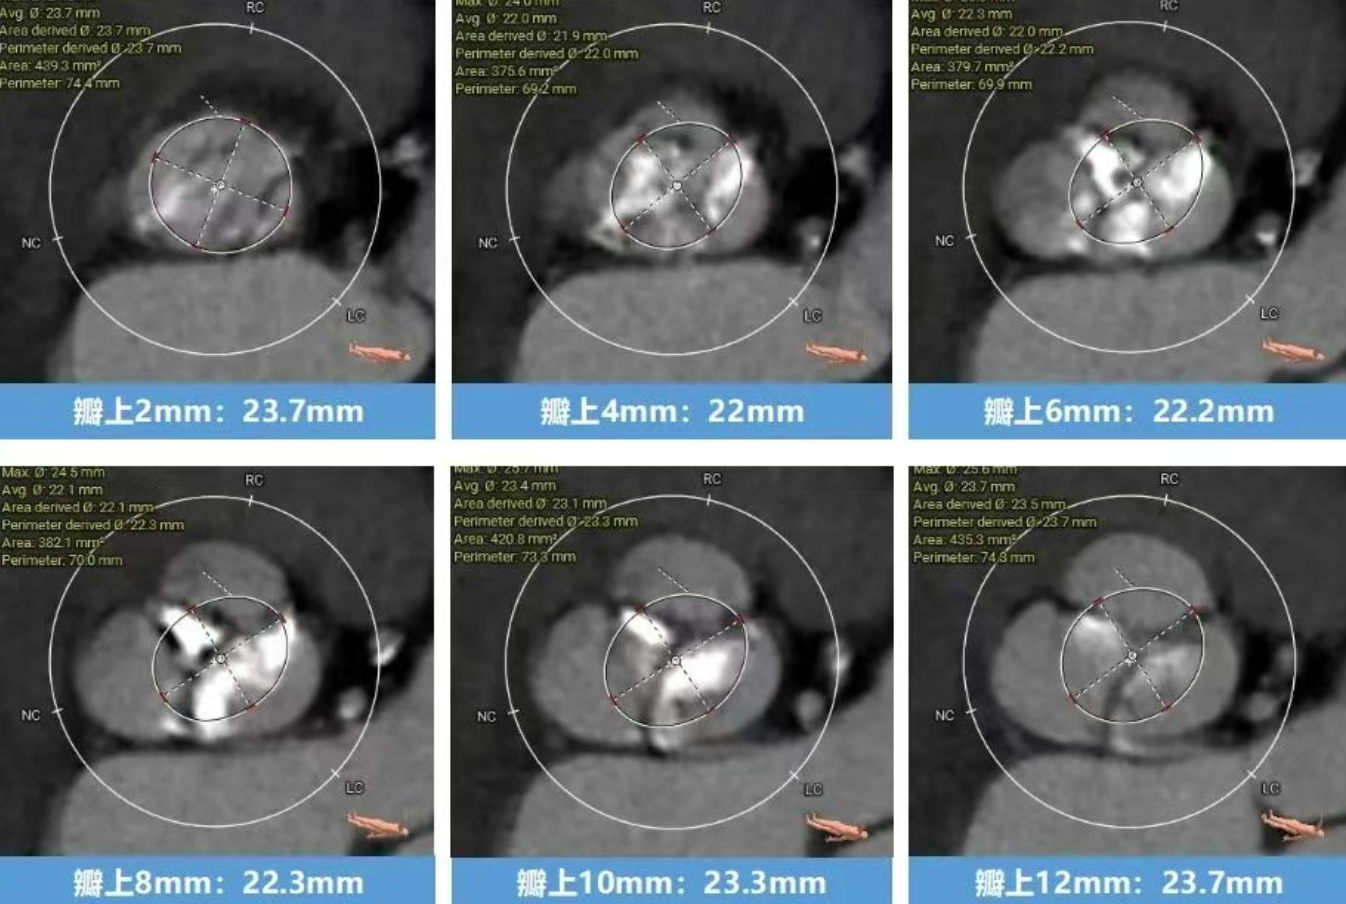

术前CT分析(76岁,女性)

▶ Type1型二叶式主动脉瓣(L-R),瓣叶增厚,重度钙化,钙化分布不均匀,无窦钙化延申至STJ以上,LVOT偏直筒型。

瓣上结构测量